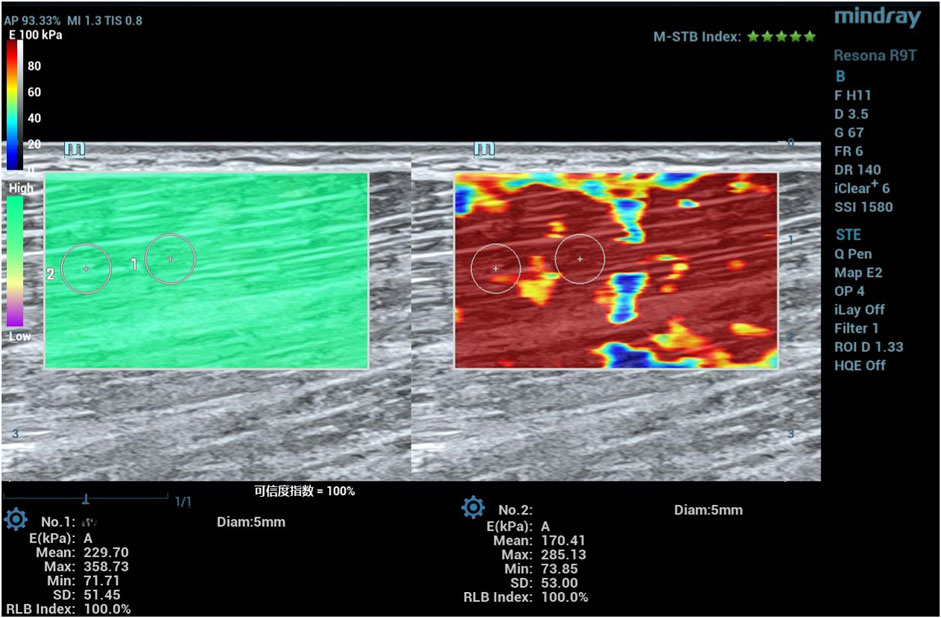

This randomized controlled trial aimed to compare the acute and sustained effects of tissue flossing (TF) versus dynamic stretching (DS) on hamstring muscle stiffness and flexibility in light volleyball enthusiasts. Thirty-seven participants were randomly assigned to TF, DS, or placebo groups. Muscle stiffness was evaluated using shear-wave elastography, measuring Young's modulus at distal and proximal regions of the biceps femoris long head and semitendinosus. Flexibility was assessed via passive knee extension (KE), straight leg raise (SLR), and forward flexion distance (FFD) at baseline, immediately post-intervention, and minutes post-intervention. The results demonstrated that TF significantly reduced muscle stiffness compared to DS at the 30-minute mark, particularly in the semitendinosus (distal: mean difference = –43.40 kPa, 95% CI [–80.65, –6.16], p = 0.007; proximal: –51.13 kPa, [–101.20, –1.05], p = 0.040). However, no significant differences were observed between TF and DS groups in flexibility outcomes (KE, SLR, or FFD) at any time point. These findings indicate that while TF offers a prolonged reduction in hamstring stiffness—suggesting potential benefits in injury prevention and prolonged performance—its effect on functional flexibility remains comparable to that of dynamic stretching. TF may serve as an effective warm-up intervention for athletes requiring sustained decreases in muscle stiffness during activities.